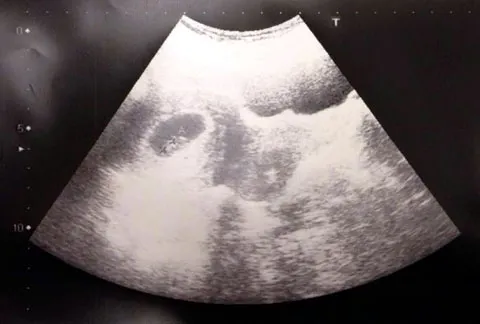

瞄了一眼顯示「確定是懷孕了」的訊息,